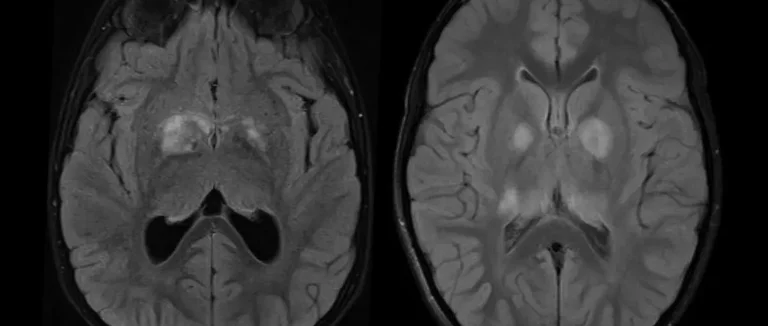

Caractéristiques radiologiques des tumeurs sur les images CT

Les tumeurs cérébrales ont des traits uniques sur les images CT. La taille, la forme, la localisation et la densité sont très importants. Par exemple, certaines tumeurs semblent plus claires ou plus foncées que le cerveau autour.

Les tumeurs malignes ont souvent des contours déformés. Elles peuvent montrer une prise de contraste inégale après l'injection de produit de contraste. Ces signes aident à savoir si la tumeur est maligne.

Différenciation entre tumeurs et autres pathologies cérébrales

Il est difficile de distinguer les tumeurs des autres maladies cérébrales. Les radiologues doivent examiner plusieurs conditions comme les abcès et les kystes. Une analyse détaillée des caractéristiques et de la prise de contraste est cruciale pour faire la différence.